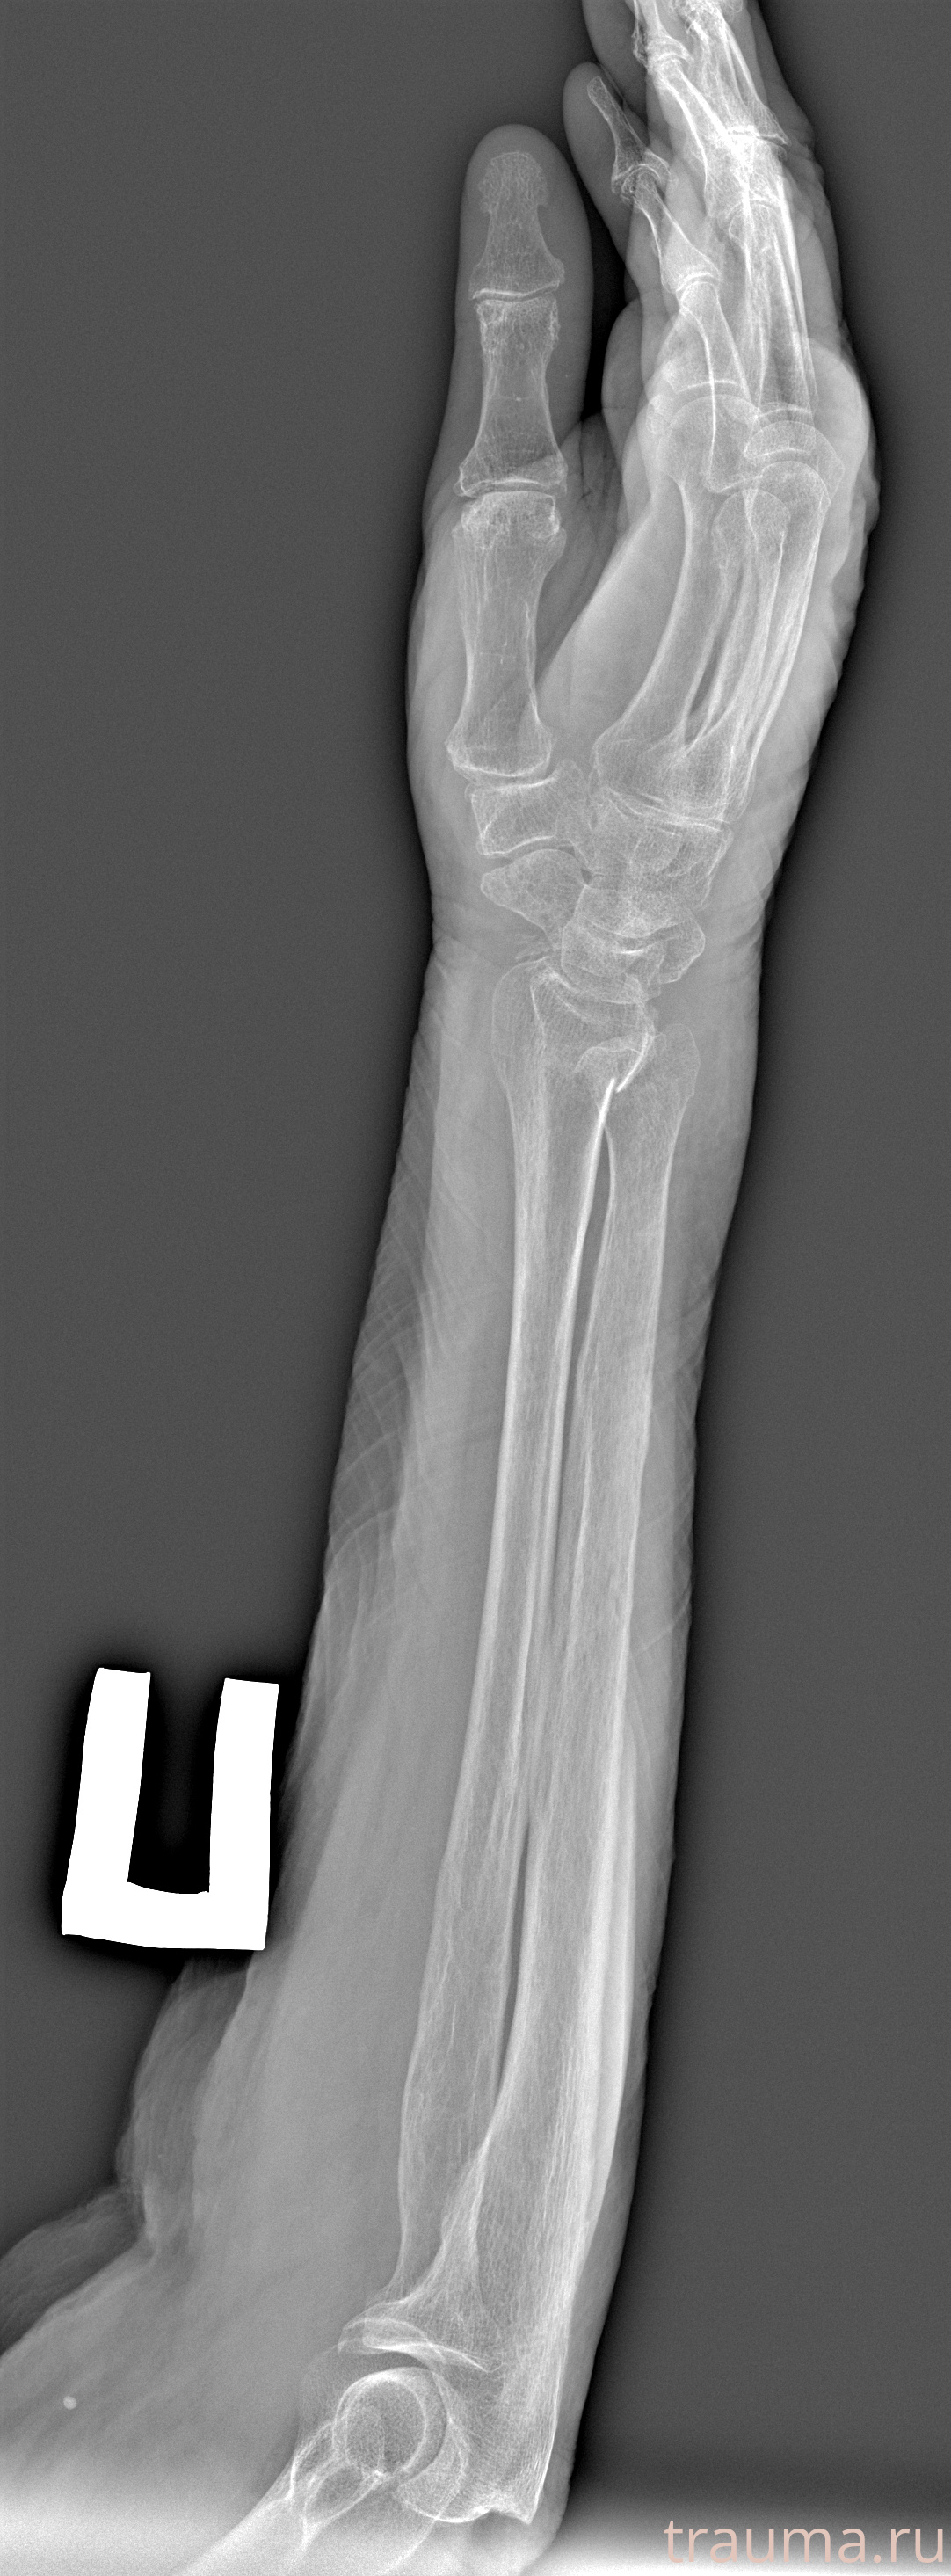

Перелом 3-5 ребер слева